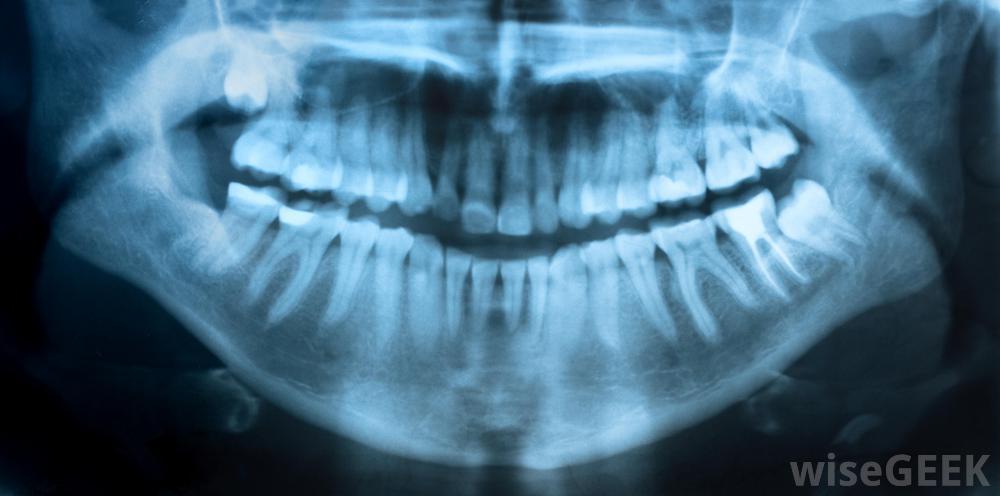

X光是根管治療的一部分。

婦女在懷孕期間對根管的主要擔憂可能是需要x光片。然而,在大多數情況下,對正在發育中的孩子的風險是最小的。進行根管治療所需的x光片是針對婦女的口腔而不是腹部,因為這可能會影響到她的寶寶。此外,如果婦女懷孕期間需要x光片,牙醫可能會提供一件鉛背心來保護她的腹部盡管如此,牙醫通常建議婦女等到分娩后才進行常規x光檢查;只有那些對根管或其他牙科手術絕對必要的檢查通常在懷孕期間進行。

數字放射技術允許牙醫對患者進行x光檢查;牙齒不會暴露在危險的輻射水平下。